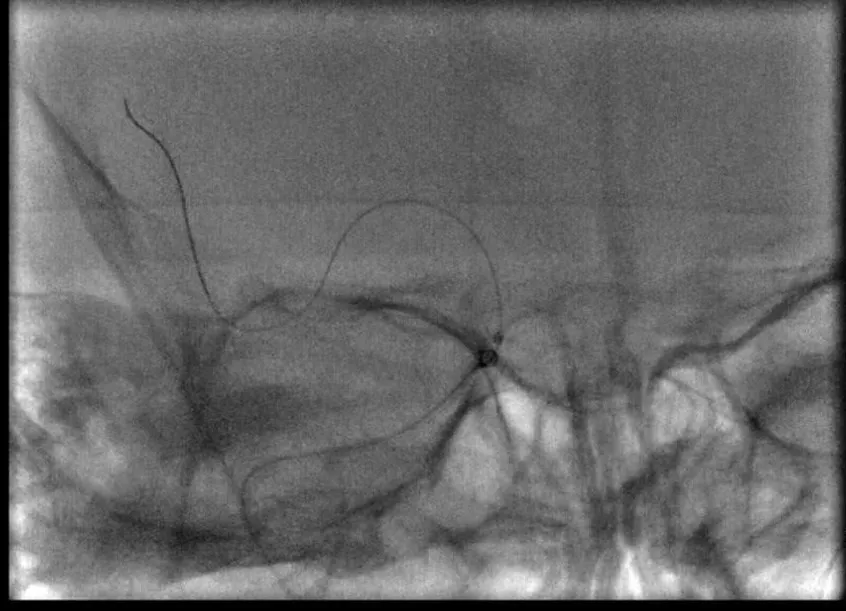

8F指引导管联合6F Navien中间导管,右侧MCA取栓:微导丝到位;Rebar27导管到位,冒烟证实于血管腔内;6*30mm支架放置MCA-M1段,MCA未见显影,ACA未见显影;表明血栓负荷非常大

中间导管到位后,因根据平时实践,此时拉栓的成功率非常低,故未行拉栓。再次置入一个微导丝于ACA,微导管置入后冒烟证实于真腔内。之后放置两个支架,MCA中使用6*30mm,ACA中使用4*20mm。

8F指引导管联合6F Navien中间导管,右侧ACA取栓:微导丝到位;Rebar18导管到位,冒烟证实于血管腔内;Solitaire 4-20支架放置ACA-A1分支内

造影后发现,右侧ACA部分再通,MCA仍闭塞。支架静置4分钟后造影提示显影更差。

双支架放置后造影提示,右侧ACA部分显影,MCA仍血管显影不佳(A),双支架放置4分钟后造影提示,右侧前循环显影更差(B)